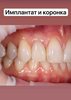

· Полный цикл ортопедической реабилитации: от подготовки (имплантация, НКР) до фиксации постоянных конструкций (цирконий, металлокерамика, съемные протезы).

Опытный хирург-имплантолог с более чем 8-летним стажем. Специализация на комплексной реабилитации (All-on-4/6, полная дуга), сложной костной пластике (синус-лифтинг) и эстетической хирургии мягких тканей. Владею цифровыми протоколами планирования и лечения. Постоянно совершенствую навыки через участие в международных конгрессах и курсах (Kisir Academy, Simko, Aurum). Нацелен на внедрение передовых хирургических методик и обеспечение предсказуемых результатов лечения.

· Комплексная имплантация: All-on-4, All-on-6 (FP-1), одномоментная и отсроченная имплантация.

· Хирургия мягких тканей: пластика рецессий (tunneling technique), вестибулопластика, пластика уздечек, закрытие соустья.